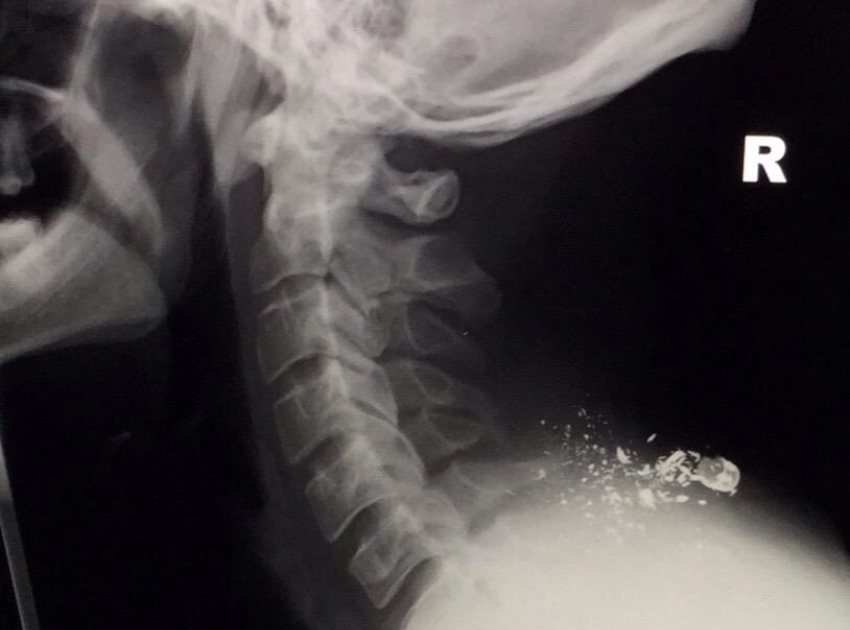

In 2010, while serving in Afghanistan, Mark Harding was shot through the neck, resulting in the complete shattering of his C5 and C6 spinal segments and paralysis from the neck down. Despite being told multiple times that he would never walk again, Mark defied the odds and started to regain some movement. Last year, he completed a challenge that his doctors would have thought impossible – walking for 85 days across the entire length of the UK, from John O’Groats to Lands’ End, using crutches, raising over £36,000 for Scotty's Little Soldiers.

Side x-ray showing shrapnel still in Mark's body